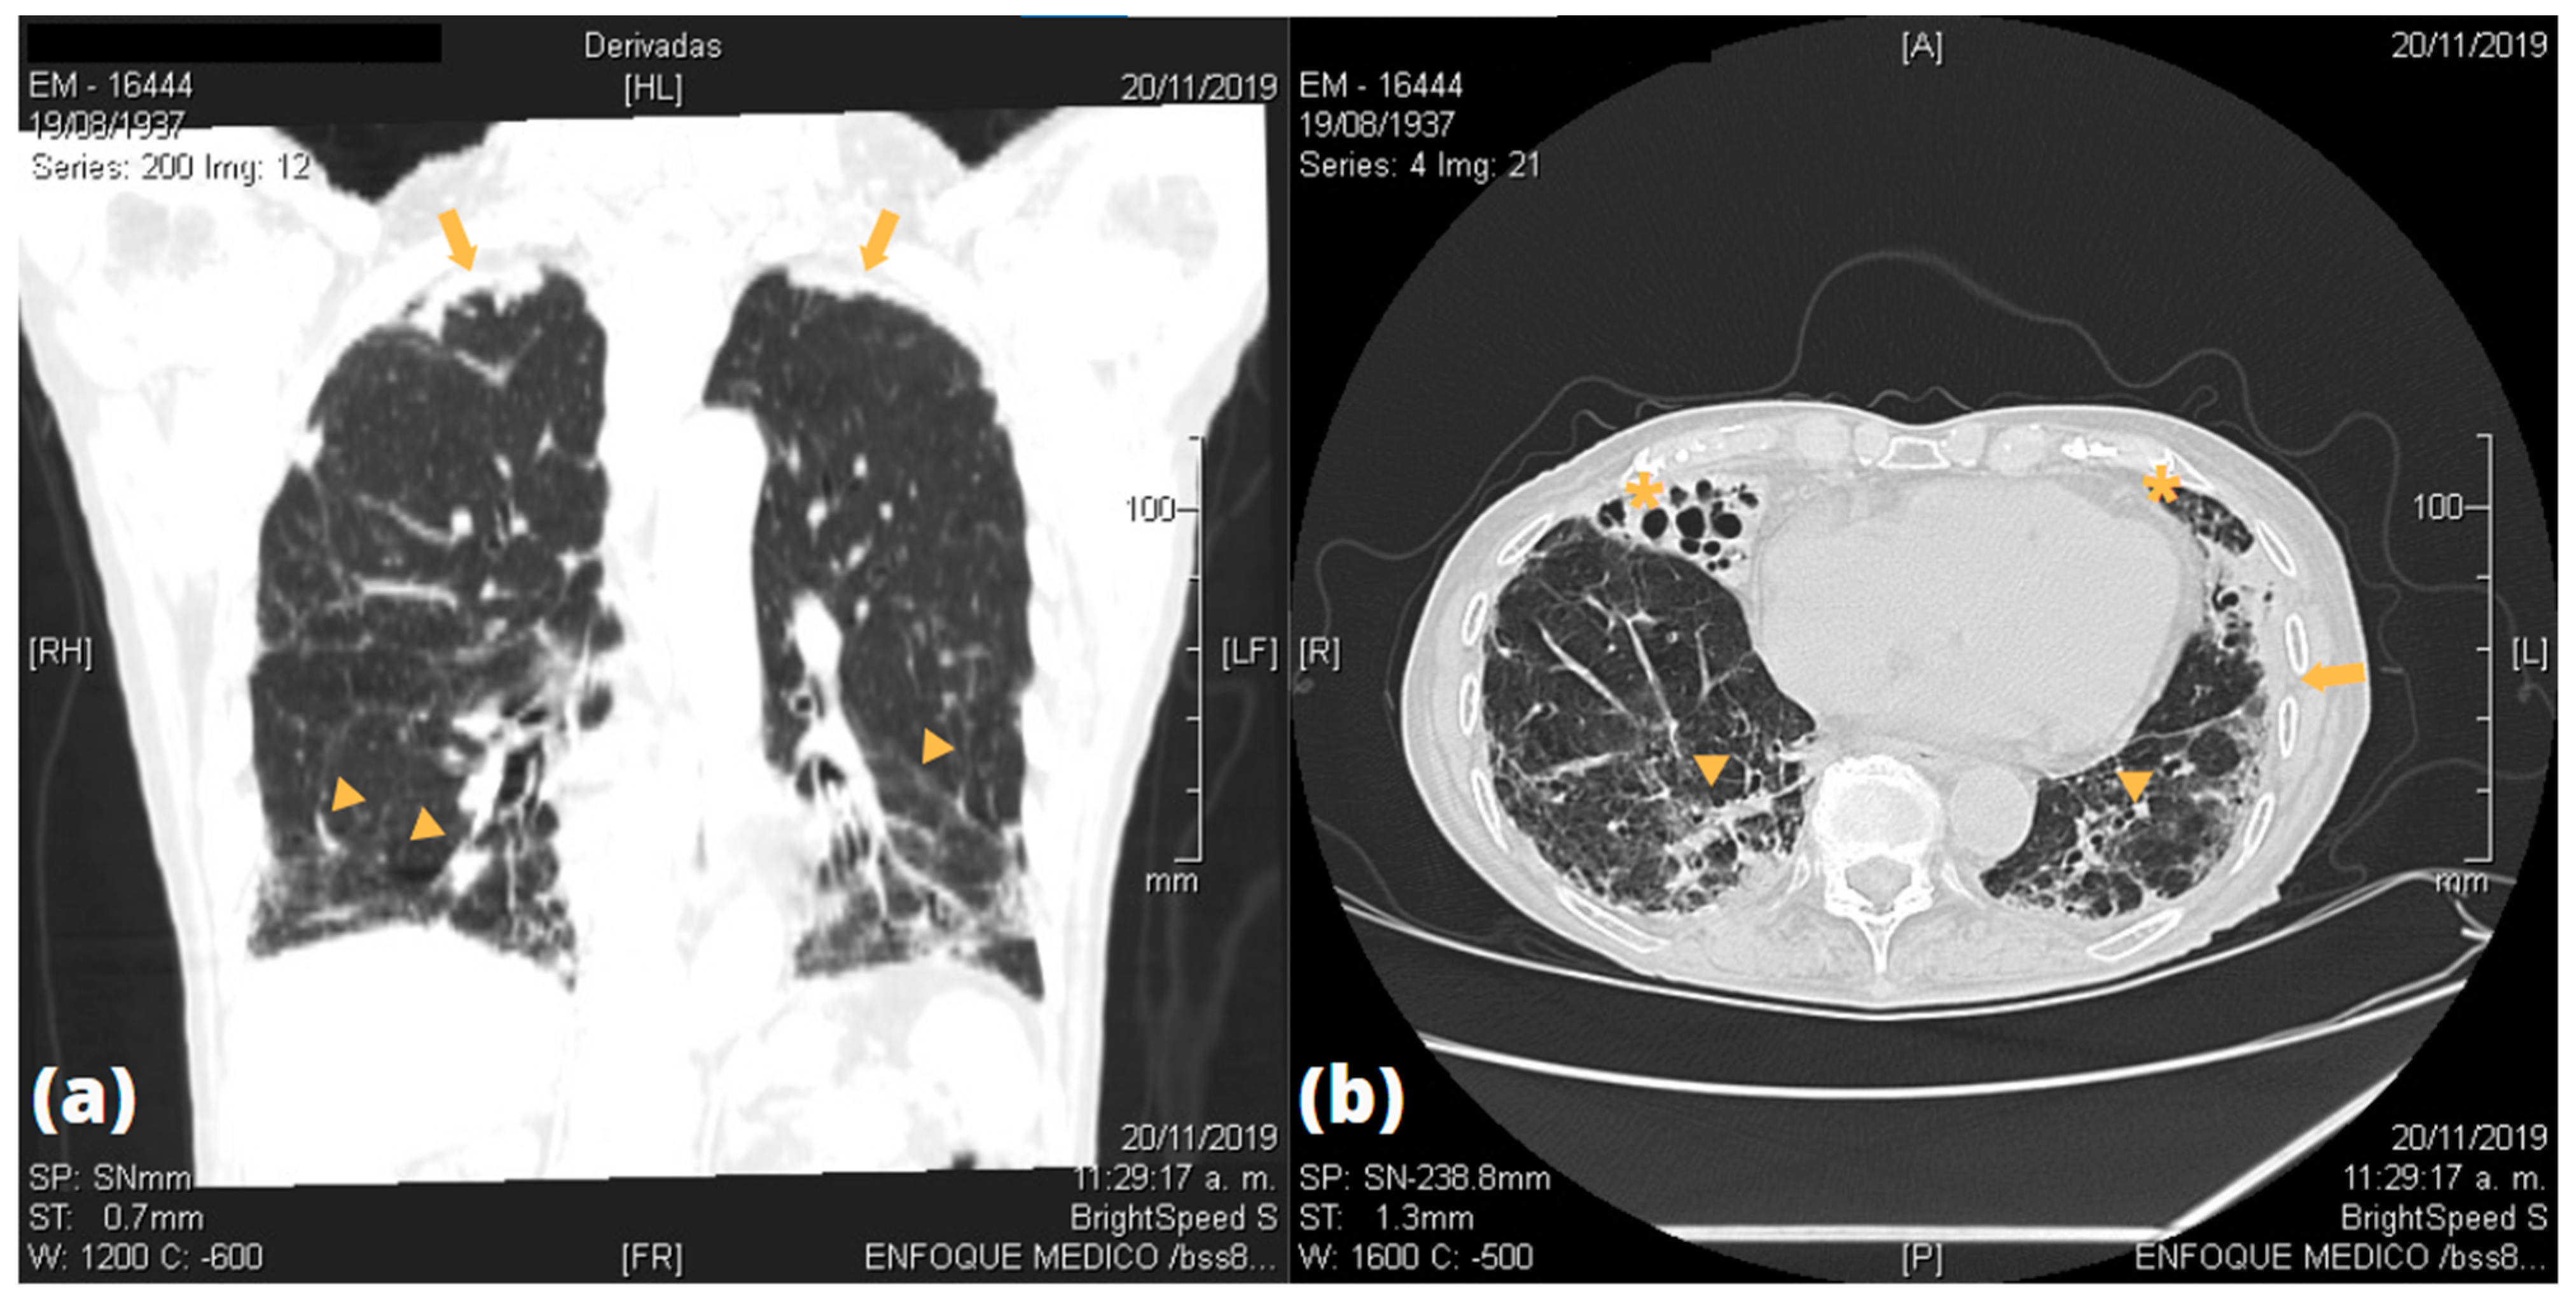

| Patients | Bronchial Lesion | Alveolar Lesion | Parenchymal Lesion | Pleural Lesion |

|---|---|---|---|---|

| P1 | None | None | Scarce right inferior fibrous sequelae tracts | None |

| P2 | Bilateral tubular bronchiectasis | None | Bilateral GGO; scarce right inferior fibrous retractile tracts | None |

| P3 | Bilateral varicose bronchiectasis | None | None | None |

| P4 | None | None | Bilateral apical fibrous retractile tracts | Bilateral apical pleural thickening |

| P5 | Right medial bronchiectasis | None | Bilateral inferior GGO; bilateral apical fibrous retractile tracts; right medial air cyst | Bilateral apical pleural thickening |

| P6 | Right medial and left inferior bronchiectasis | None | Bilateral inferior fibrous retractile tracts; right apical interstitial infiltrate | None |

| P7 | Left atelectasis | None | Bilateral inferior interstitial infiltrate | None |

| P8 | Bilateral cylindrical hilio-perihiliar bronchiectasis; laminar atelectasis | None | Bilateral apical fibrous retractile tracts | Right apical pleural thickening |

| P9 | Bilateral tubular bronchiectasis | None | Bilateral GGO with fibrous tracts | None |

| P11 | Right medial varicose bronchiectasis | None | Bilateral inferior GGO and interlobular septal interstitial thickening; bilateral apical thick fibrous sequelae tracts | Bilateral apical pleural thickening |

| P12 | Right tubular bronchiectasis | None | Bilateral inferior opacities and fibro retractable tracts | Bilateral pleural thickening |

| P13 | Bilateral tubular and varicose bronchiectasis | None | Right inferior GGO; bilateral inferior intra- and interlobular thickening | None |

| P14 | None | None | None | None |

| P15 | None | None | Subpleural infiltrate | None |

| Radiological Lung Lesion | Frequency |

|---|---|

| Lobe compromise | |

| Lower lobe: RL, LF | 10/14, 9/14 |

| Medial lobe: RL | 7/14 |

| Upper lobe: RL, LF | 7/14, 5/14 |

| Bronchial lesions | |

| Bronchiectasis | 9/14 |

| Bilateral | 5/9 |

| Atelectasis | 2/14 |

| Alveolar damage | 0/14 |

| Parenchymal damage | |

| GGO/infiltrates | 7/14 |

| Fibro-retractable tracts | 10/14 |

| Bilateral pleural thickness | 5/14 |